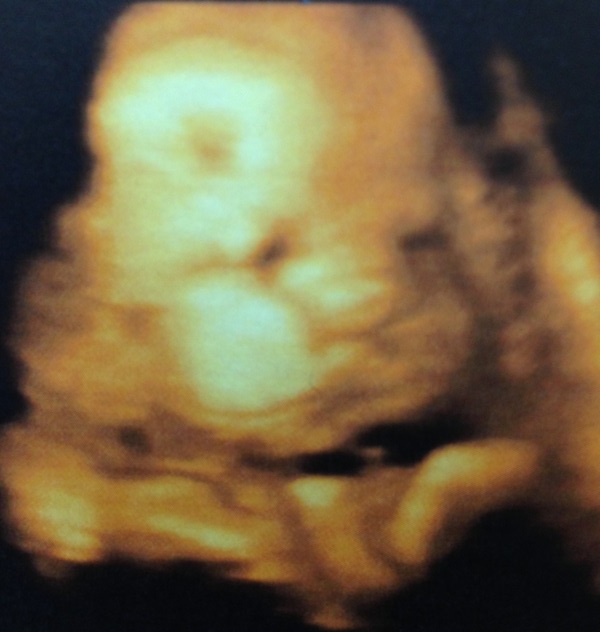

18 августа у нас была встреча с дочей на последнем узи, весила на тот момент 2330, предварительно нам предполагают рождение 3600 ( я согласна, но верится в это слабо), обмоталась один раз пуповиной ягоза, надеюсь все будет хорошо.

Вот наше щекастенькое чудо)

На родах буду ей кричать как в анекдоте: " Алиса втяни щеки, не проходим")))